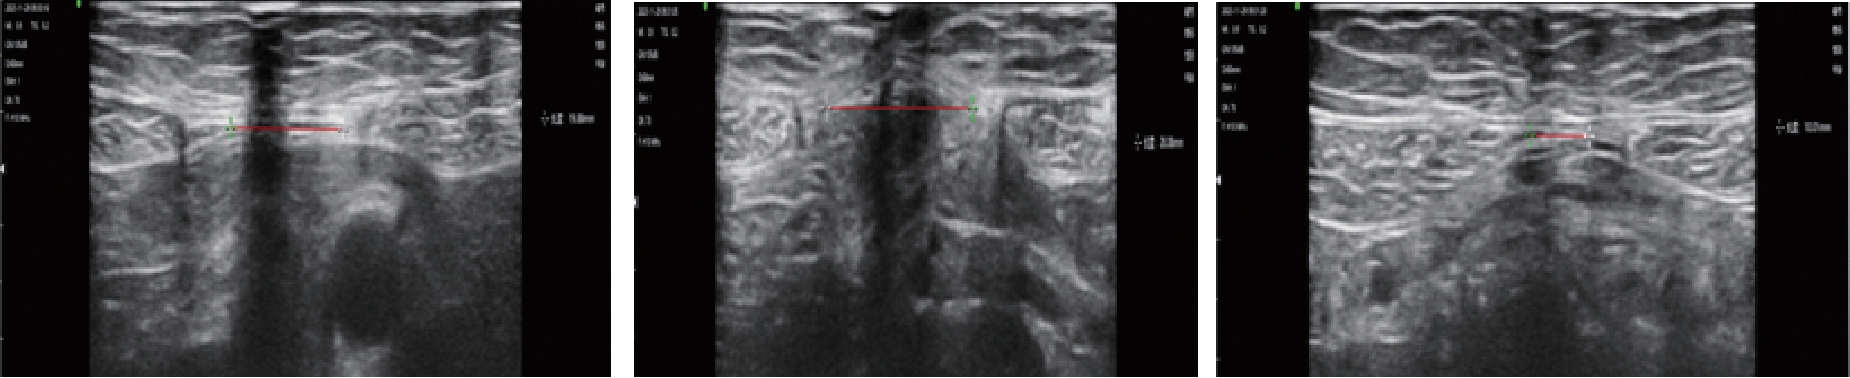

摘要:目的 探讨筋膜松解手法联合Waff核心运动在产后腹直肌分离中的应用价值。方法 选取2023年6月—2024年1月在淮安市妇幼保健院分娩的产后腹直肌分离产妇96例,采用随机分组法分为观察组与对照组,每组48例。对照组采用Waff核心运动治疗,观察组在对照组基础上联合筋膜松解手法治疗。两组康复治疗时间均为8周。比较两组的腹直肌间距(IRD)、腹直肌厚度、腰围、尿失禁、子宫脱垂、腰背部疼痛、情绪状态及生活质量评分。结果 观察组治疗后肚脐上方5.0 cm、肚脐及肚脐下方5.0 cm处IRD均小于对照组(P <0.05),观察组治疗前后肚脐上方5.0 cm、肚脐及肚脐下方5.0 cm处IRD的差值均大于对照组(P <0.05)。观察组治疗后腹直肌厚度大于对照组,腰围小于对照组(P <0.05),观察组治疗前后腹直肌厚度及腰围的差值均大于对照组(P <0.05)。观察组治疗后尿失禁和子宫脱垂症状评分均低于对照组(P <0.05),观察组治疗前后尿失禁和子宫脱垂症状评分差值均大于对照组(P <0.05)。观察组治疗后腰背部疼痛症状评分均低于对照组(P <0.05),观察组治疗前后腰背部疼痛症状评分的差值大于对照组(P <0.05)。观察组治疗后HAMA、HAMD及SF-36评分均低于对照组(P <0.05),观察组治疗前后HAMA、HAMD及SF-36评分的差值均大于对照组(P <0.05)。结论 Waff核心运动联合筋膜松解手法治疗产后腹直肌分离,有助于缩小患者的IRD,促进腹直肌恢复正常,减轻尿失禁、子宫脱垂及腰背部疼痛等症状。

摘要:目的 探讨高频超声用于评估Flexi-bar运动训练联合脉管电刺激治疗后产后腹直肌分离变化的临床价值。方法 回顾性分析常州市妇幼保健院2022年5月—2024年4月收治的87例产后腹直肌分离患者的病历资料。根据治疗方法不同将患者分成观察组(45例)与对照组(42例),观察组采用Flexi-bar运动训练联合脉管电刺激治疗,对照组采用脉管电刺激治疗。采用高频超声评估患者腹直肌间距离,对比两组的腹围、腹直肌间距离、腹直肌均方根、肌纤维力及生活质量。结果 观察组治疗前后下腹围、中腹围和上腹围的差值均大于对照组(P <0.05)。观察组治疗前后屈曲状态下脐下3 cm、脐上3 cm和脐中腹直肌间距离的差值均大于对照组(P <0.05)。观察组治疗前后静息状态下脐下3 cm、脐上3 cm和脐中腹直肌间距离的差值均大于对照组(P <0.05)。观察组治疗前后腹直肌最大自主等长收缩振幅均方根、盆底Ⅱ类肌纤维肌力平均值、盆底Ⅰ类肌纤维肌力最大值的差值均大于对照组(P <0.05)。观察组治疗前后生活质量评分的差值大于对照组(P <0.05)。结论 Flexi-bar运动训练联合脉管电刺激可改善产后腹直肌分离患者生活质量与盆底肌纤维肌力,缩小患者腹围,促进产后腹直肌分离的恢复,且高频超声可有效评估患者恢复情况与腹直肌分离情况。